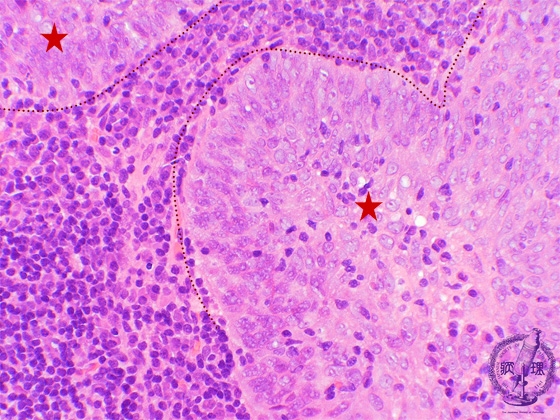

- ★(4)Nasopharyngeal carcinoma (lymphoepithelioma)

e tumor cells in this example show better differentiation as compared to the tumor cells in undifferentiated carcinoma. The tumor cells are invasive, show sheet-like proliferation and form large alveolar lesions (asterisk). Central nucleoli are not prominent and show similar features of squamous cell carcinoma.